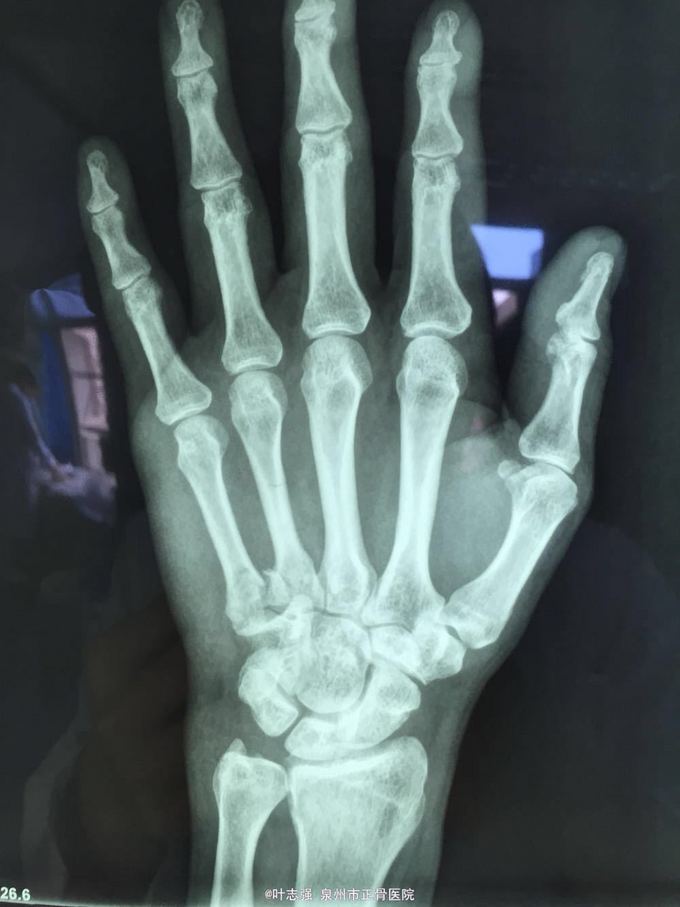

右手第5掌骨基底部骨折

右手第5掌骨近端肿胀,局部压痛骨擦感,掌指关节活动受限。

右手第5掌骨基底部粉碎骨折 予手法整复夹板外固定6周,定期复查调整透视。